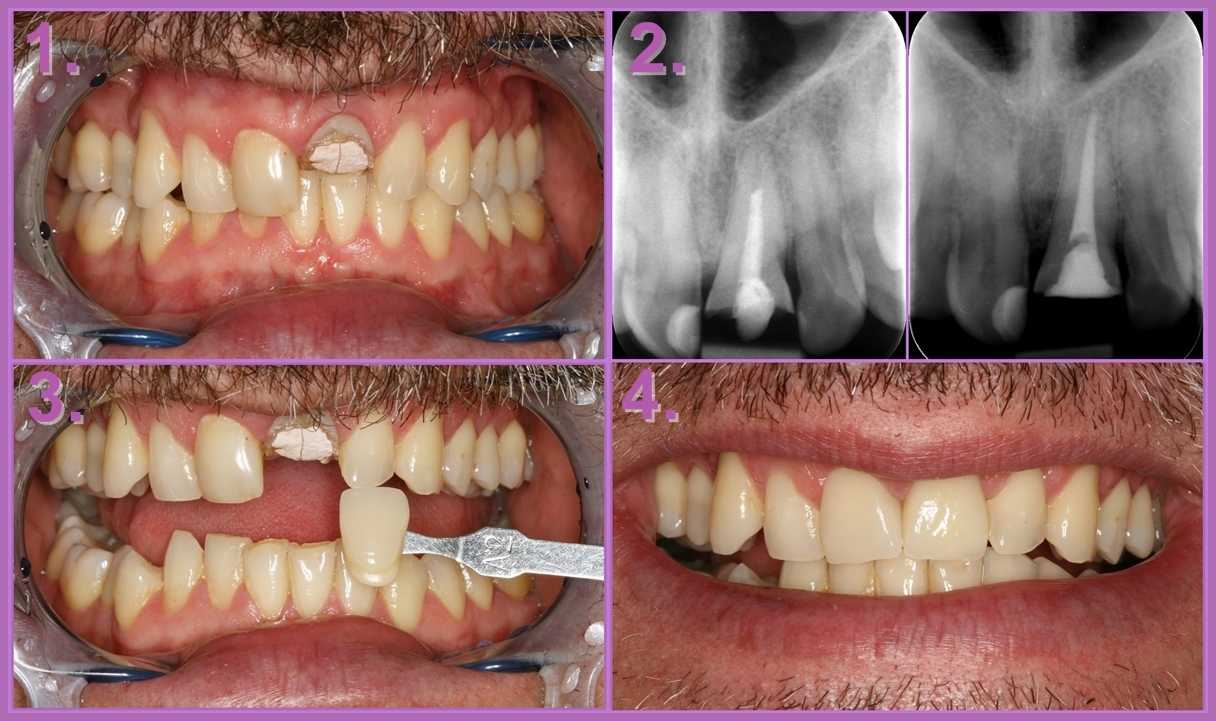

A következő esettanulmányból kiderül, milyen kiváló megoldást jelenthet egy eMax korona.